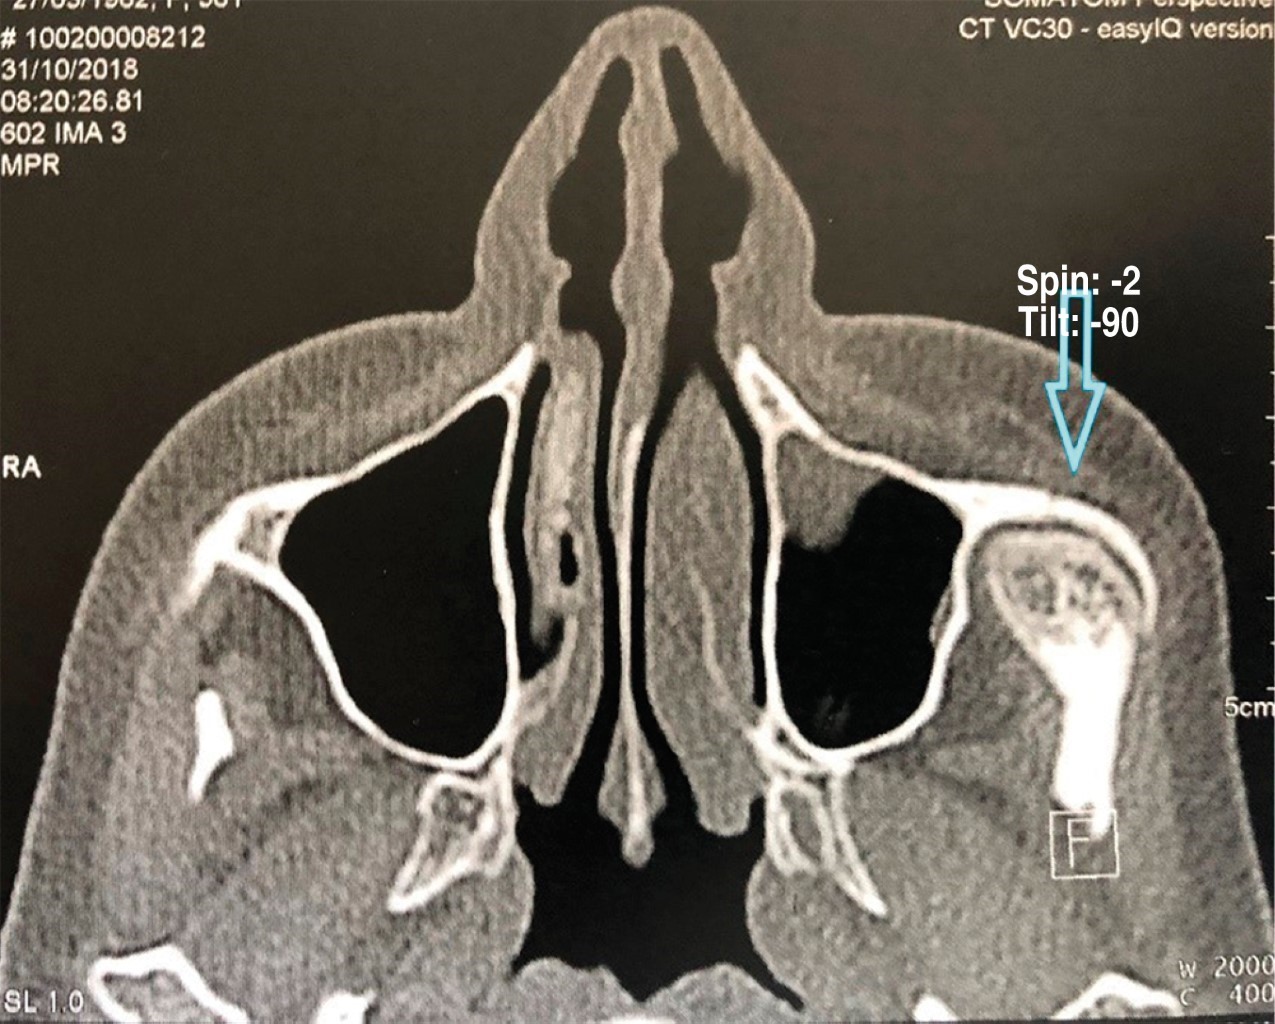

En la RMN se observa una lesión en la apófisis coronoides del lado izquierdo (Figura 4). En la ciudad de Bahía Blanca, Buenos Aires, Argentina donde desarrollamos nuestra práctica, no contamos con tomógrafo computarizado de haz cónico de Fov amplio, por lo tanto, se solicita una tomografía computarizada multislice, en la cual se verifica una lesión tumoral en la apófisis coronoides izquierda con forma de hongo, que se introduce entre el arco cigomático y el maxilar desplazando ambas estructuras (Figuras 5 y 6).

Figura 5

Figura 6